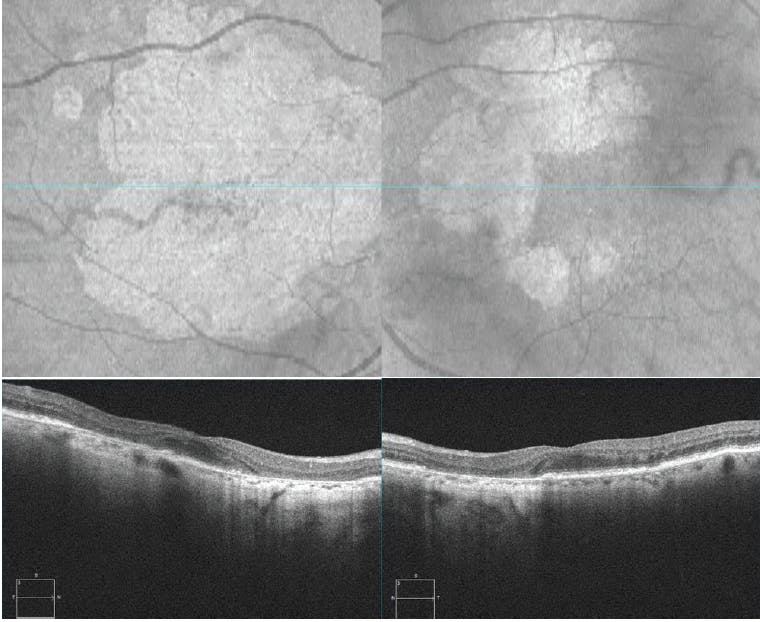

An 89-year-old woman with dry AMD presented to the clinic with BCVA 20/25 OU. OCT imaging revealed GA lesions in the extrafoveal regions OU, with slightly more developed lesions OD (Figure 3). Approximately 4 years later, the patient returned with BCVA 20/50-1 OD and 20/40+1 OS; BCVA for this and all follow-up appointments can be viewed in the Table.

<p>Figure 3. En face and B-scan imaging shows early evidence of atrophy OU, with more pronounced extrafoveal lesion development OD compared with OS.</p>

Figure 3. En face and B-scan imaging shows early evidence of atrophy OU, with more pronounced extrafoveal lesion development OD compared with OS.